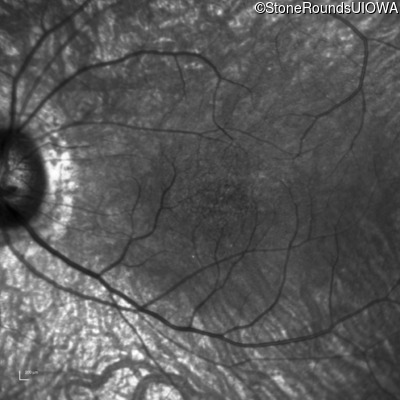

Infrared Fundus Photograph - Right - 20/40

Exemplar